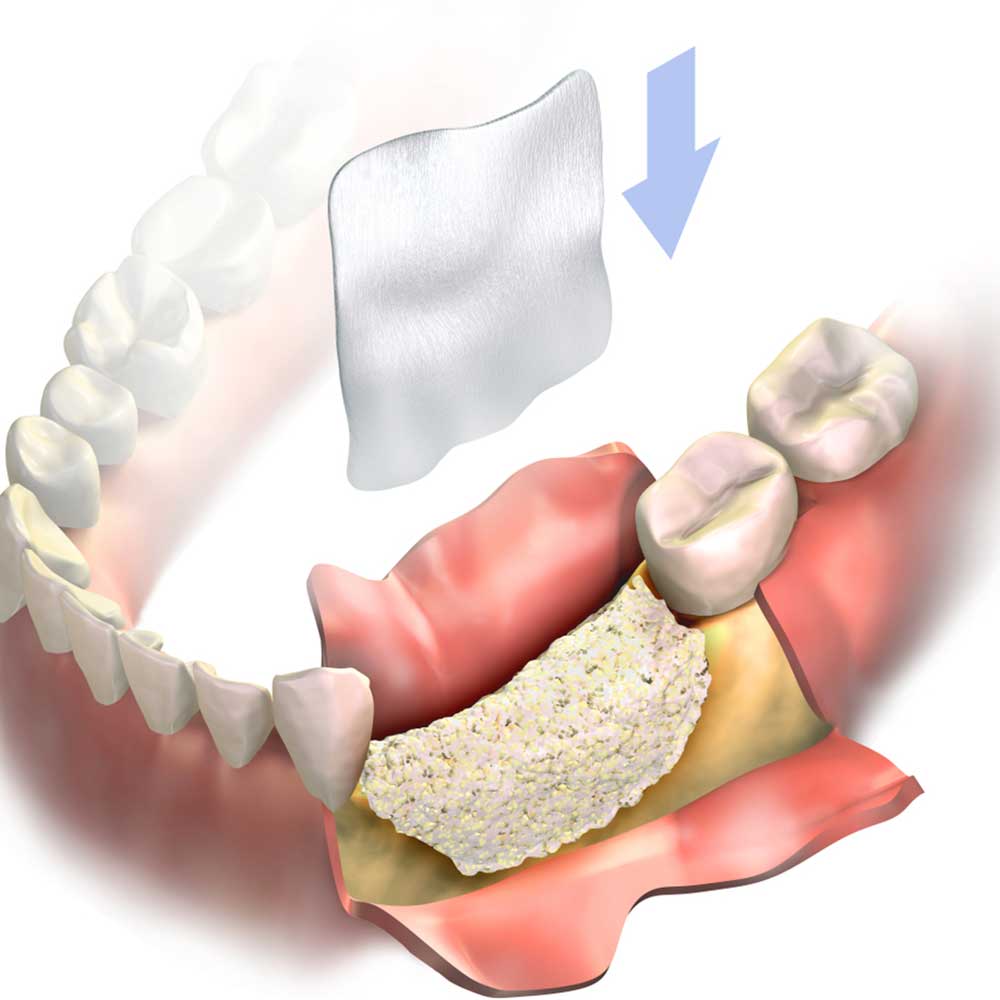

What Is Bone Grafting?

Bone grafting is a surgical procedure in which fractures or cracks in bones are repaired. This is typically done by stabilizing the broken or cracked bone using fixation materials such as surgical screws, plates, wires, or screws. The goal of this procedure is to restore the alignment of the bones and provide the necessary stability to promote proper bone healing.

What Is Bone Graft?

A bone graft is a surgical procedure used to repair fractures or tears in bones by fixing the damaged bone pieces using plates or surgical screws, usually in the form of a patch on the bone’s surface. Bone grafts help restore bone stability, promote healing, and are used in a variety of cases that require surgical bone fixation, including:

What Are the Different Types of Bone Grafts?

Many doctors and specialists emphasize that bone grafts vary and diversify, with some notable examples of this diversity, including:

- Autografts: These are grafts taken from the patient themselves, including cortical and cancellous bone grafts.

- Allografts: These are grafts taken from a donor of the same gender.

- Xenografts: These grafts primarily come from surrounding animals.

Each type of graft has its own unique characteristics and advantages, and the choice of graft type depends on the patient’s specific medical condition and needs.

Places to Obtain Autografts

In most cases, many doctors emphasize that it is possible to perform what is known as autografting. This type of procedure depends on choosing the source of the bone graft, which is based on various factors related to size, shape, strength, the ability to stimulate recovery and healing. Some of the prominent places where autografts can be obtained include:

- Pelvic bones.

- Shins.

- Ribs.